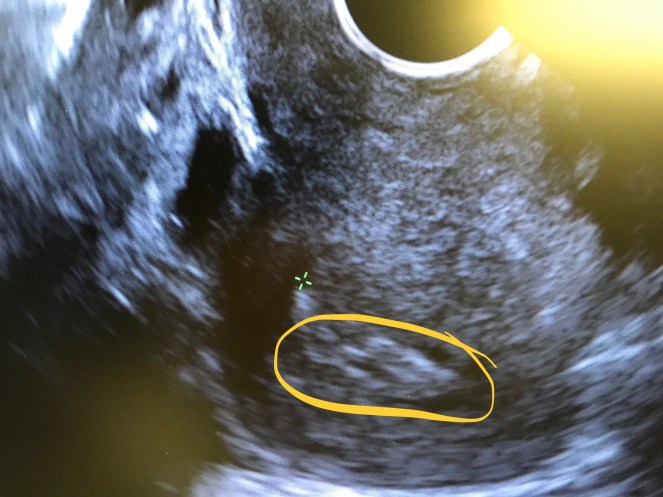

The lights were then turned down low, the Marvin Gaye started in the background and the ultrasound wand was inserted. Seconds after insertion by M, DRW came in to view the results. It was all very exciting. I certainly felt celebrated at that moment – more so than I have in years. There were movie quotes from Clint Eastwood in Sudden Impact that I didn’t quite get the references to and a lot of jovial noises all around. Then, we discussed the ultrasound – the lining was about 9 MM and had the trilaminar appearance that is important structurally. See below for a picture of my uterus – the three lines are circled for your viewing convenience. It’s not the best picture because I didn’t get the close-up (I sneak pictures after we’re done. I’m sure I could probably just ask, but for whatever reason, I haven’t yet.) Ignore the constant cysts that are impeding upon my reproductive system.